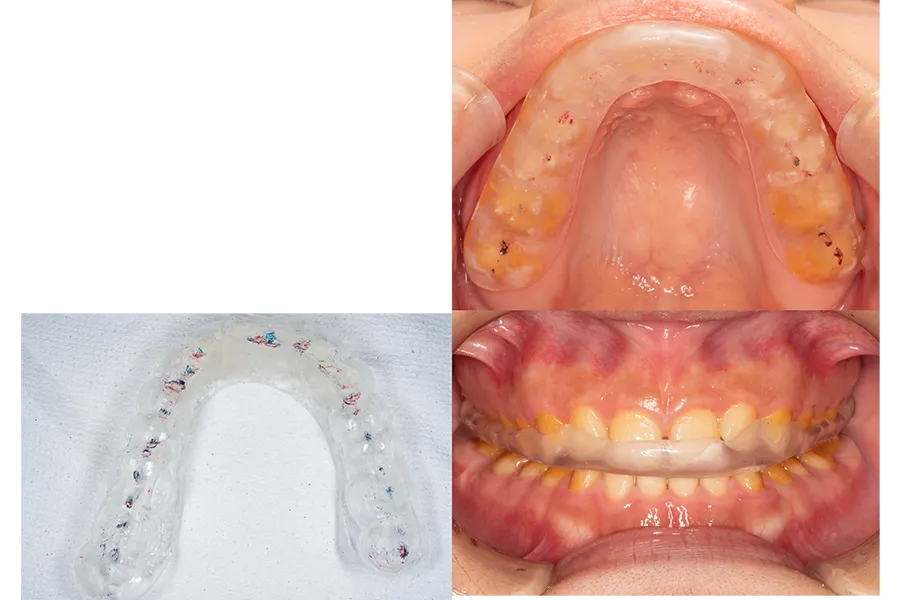

スプリントによる顎位の確認

咬み合わせの位置を安全に変更するため、スプリント療法を行い顎関節と咀嚼筋の状態を確認しました。

顎位の安定を確認したうえで、最終補綴へと移行しています。